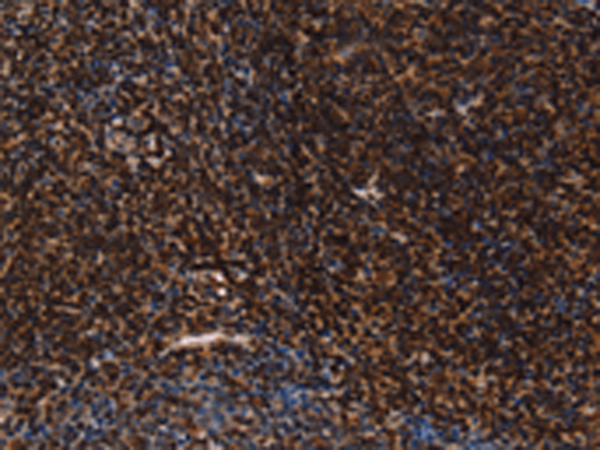

分类: 科研抗体货号: P07408别名: hK1; KLKR; Klk6应用: IHC反应种属: Human